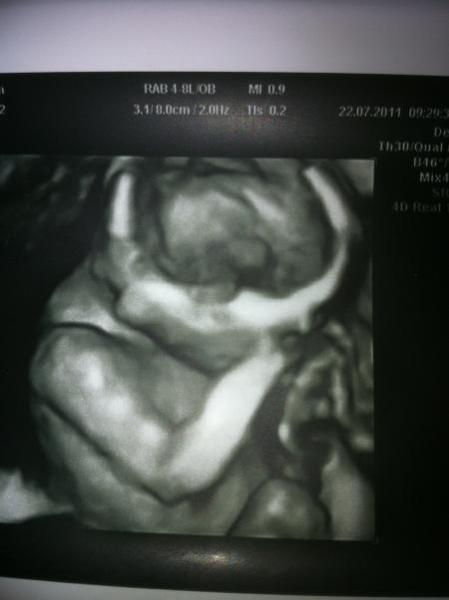

hall hr lieben...es war soooooooo schön beim artzt heut...is alles super in ordnung..ärztin sagt kann nicht besser sein...alles dran und drin was baby braucht......fruchtwasser auch ok und plazenta auch........und jetz wollt ihr es bestimmt hören ..... mädchenfront rückt auch näher ...mein mann war mit und soo neugierig und fagte die ärztin wo der kleine zipfel wär....hahhahahaaa da sagte sie da gibts kein...das gesicht hättet ihr sehen müssen...süss.....aber er freut sich riesig....hauptsach gsund.....so photo stell i glei rein...ich hoff man siehts supa...is 4 d........allen ein lieben gruss und dickes bussi an euch.........ach ja und mädchennamen sinn auch einfacher zu finden...hihi....

so da ist sie....231g und 20cm.....